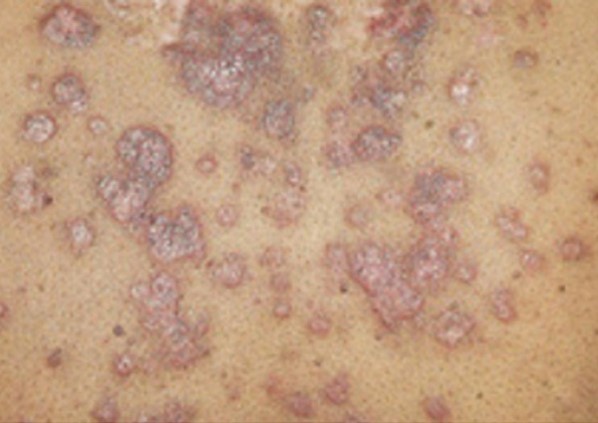

PSÖRİAZİS VULGARİS

Psoriazis çeşitli klinik biçimlerde ortaya çıkabilen, yineleyici, kronik bir deri hastalığıdır. Deri lezyonlarının çok tipik olması nedeniyle tanı koymak oldukça kolaydır. Lezyonlar klasik olarak eritroskuamozdur; bu hem vasküler yapıların (eritem) hem de epidermisin (skuam) etkilendiği gösterir. Morfolojik olarak çok değişik biçimlerde görülür. Psoriazis vulgaris en sık rastlanan tipidir.

ClosePSÖRİAZİS VULGARİS

Psoriazis çeşitli klinik biçimlerde ortaya çıkabilen, yineleyici, kronik bir deri hastalığıdır. Deri lezyonlarının çok tipik olması nedeniyle tanı koymak oldukça kolaydır. Lezyonlar klasik olarak eritroskuamozdur; bu hem vasküler yapıların (eritem) hem de epidermisin (skuam) etkilendiği gösterir. Morfolojik olarak çok değişik biçimlerde görülür. Psoriazis vulgaris en sık rastlanan tipidir.